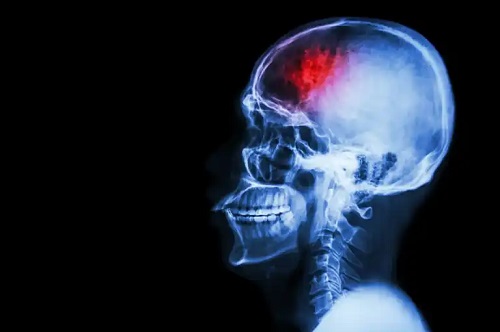

- Accident vascular cerebral: apare din cauza unei hemoragii în interiorul creierului sau unui cheag care blochează fluxul de sânge. Unul dintre simptomele comune este o durere de cap destul de severă, care apare brusc.

- Tumoră cerebrală: nu provoacă întotdeauna semne specifice, dar se poate exprima printr-o cefalee bruscă și intensă.